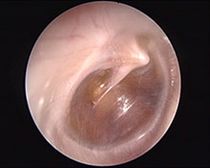

Paukenerguss (rechtes Ohr)